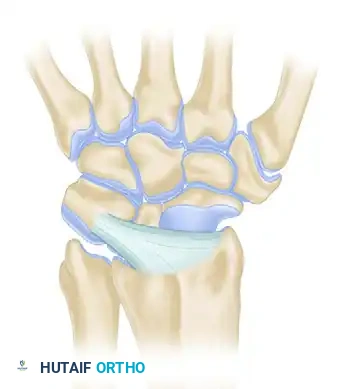

Carpal Ligamentous Architecture

Carpal stability relies entirely on its complex ligamentous network, divided into intrinsic (interosseous) and extrinsic (capsular) ligaments.

Palmar (Volar) Ligaments

Palmar ligaments are thicker and mechanically stronger than their dorsal counterparts. They form a double-V configuration that guides carpal kinematics and prevents volar intercalated segment instability (VISI) or dorsal intercalated segment instability (DISI).

Extrinsic Palmar Ligaments:

* Radioscaphocapitate (RSC): Acts as a fulcrum for scaphoid flexion.

* Long Radioscapholunate (LRSL): Primarily a neurovascular conduit rather than a mechanical stabilizer.

* Short Radiolunate (SRL): Primary stabilizer of the lunate to the radius.

Intrinsic Palmar Ligaments:

* Scapholunate (SL) Interosseous Ligament: The dorsal band is the thickest and most critical for stability.

* Lunotriquetral (LT) Interosseous Ligament: The volar band is the thickest and most critical for stability.

Dorsal Ligaments

Dorsal ligaments are thinner but crucial for preventing dorsal carpal subluxation. They are categorized by their morphological variations.

Comprehensive Dorsal Perspective:

The dorsal intercarpal (DIC) and dorsal radiocarpal (DRC) ligaments form a horizontal "V" that stabilizes the proximal row during wrist flexion.